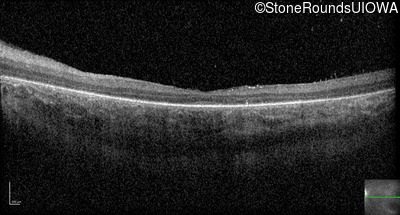

Optical Coherence Tomography - Right - 20/80 -1

Exemplar / OCT Stack